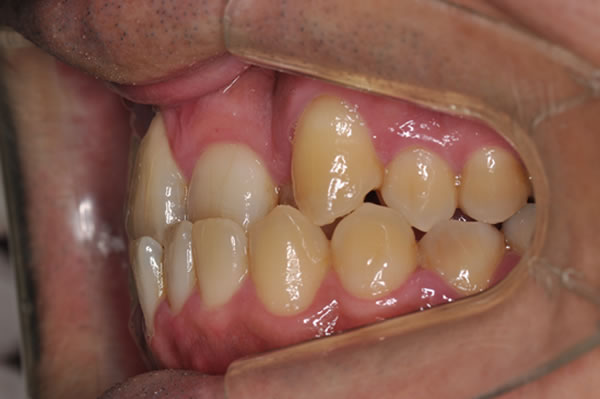

反対咬合症例

治療前(初診)